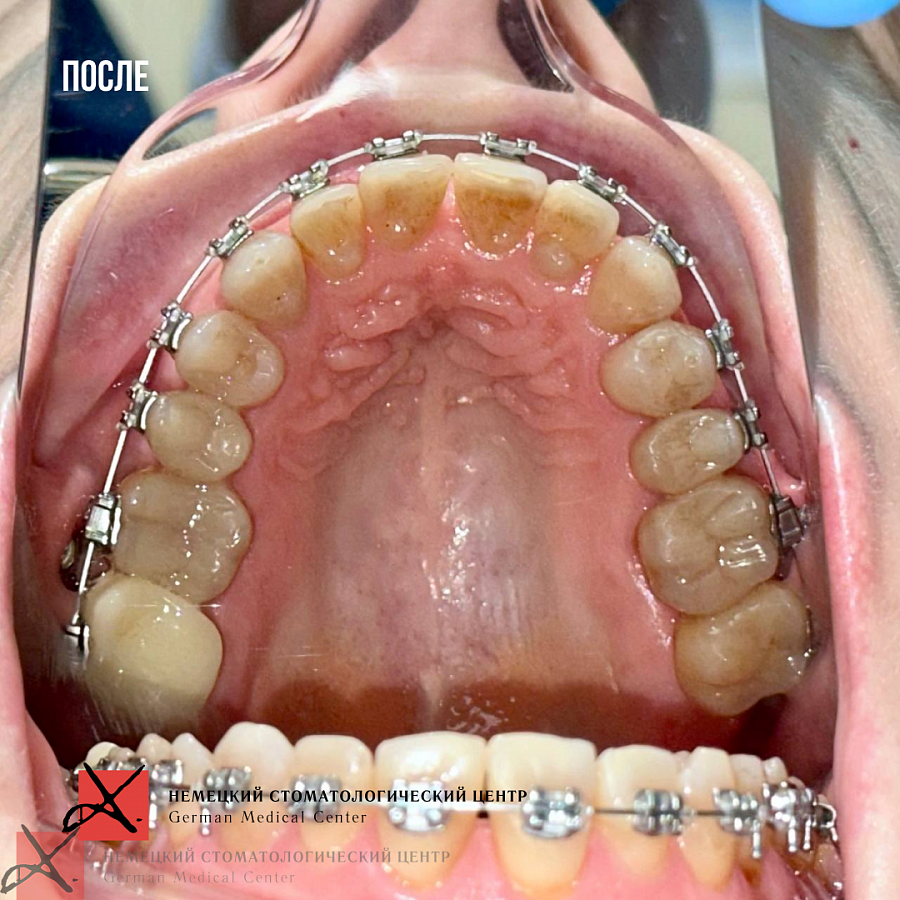

4. Ортодонтическое лечение на брекетах с применением мини-имплантатов.

На данный момент пациентка в процессе ортодонтического лечения брекетами. Боли в ВНЧС ушли. Промежуточный результат по эстетической части уже впечатляет (и нас, и пациентку).